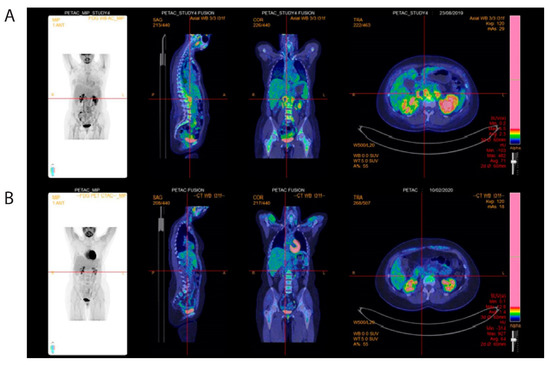

2. Case Presentation